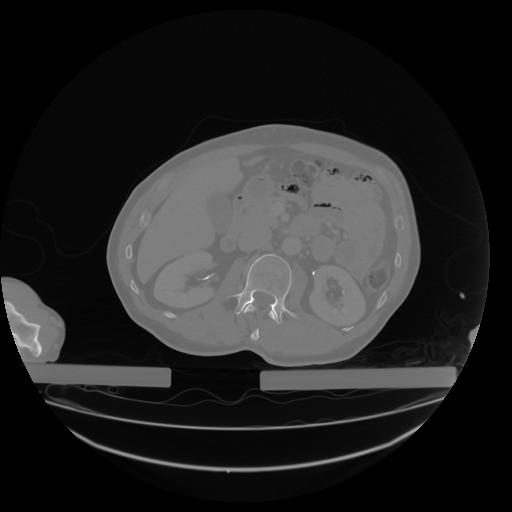

27 CUERPO,CE,Axial,3.0,CUERPO,,